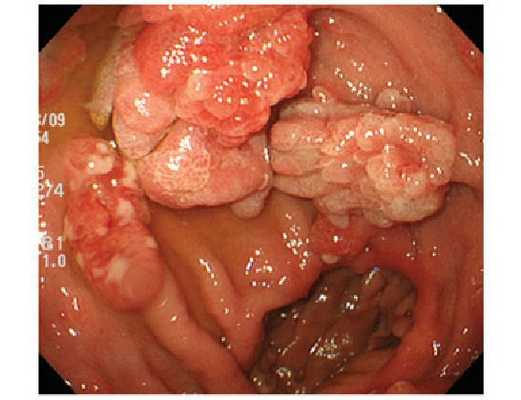

- Ворсинчатые (папиллярные) полипы толстой кишки. Выявляются у 14% пациентов. Представляют собой узлы или стелющиеся образования, имеющие насыщенный красный цвет из-за большого количества кровеносных сосудов. Могут достигать 3-5 и более см. Ворсинчатые полипы часто изъязвляются и кровоточат, возможно образование участков некроза. Обладают высокой склонностью к малигнизации.

Характерных признаков, указывающих на наличие полипов в толстом кишечнике, не существует. Кроме того, полипы кишечника этой локализации часто формируются на фоне другой патологии, воспалительного процесса. Бессимптомное течение полипов кишечника отмечается только при наличии одиночного полипа толстой кишки не более чем у 3% пациентов. У остальных чувство дискомфорта в кишечнике появляется за несколько лет до разворачивания клинической картины полипа. Практически 90% больных отмечают выделение слизи или крови во время дефекации (чем ниже расположен полип, тем ярче кровь, меньше смешивается с каловыми массами); каждый второй отмечает чередование поносов и запоров, сочетание данной симптоматики с тенезмами. На фоне диффузного полипоза клиническая картина настолько яркая, что может имитировать тяжелую кишечную инфекцию. Очень часто отмечаются боли в животе, зуд и жжение в прямой кишке и анусе. На фоне поносов и кишечного кровотечения начинает страдать и общее состояние пациента – появляется слабость, бледность, головокружение, истощение.